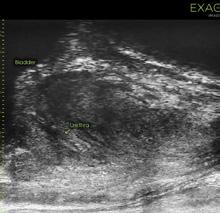

Microultrasonografia este un sistem nou de imagistică, care este conceput pentru a îmbunătăți detecția cancerului de prostată, putând fi folosit pentru a descrie leziunile suspecte pentru cancerul de prostată, dar și pentru a putea realiza o biopsie ghidată ecografic prin abord transperineal sau transrectal.

Noul sistem de microultrasonografie este mult superior sistemelor ecografice convenționale, datorită faptului că prezintă o rezoluție înaltă de 29 MHz, în comparație cu sistemele ecografice convenționale care funcționează la 9-12 MHz. Astfel rezultă o îmbunătățire cu 300% a rezoluției, lucrând la o frecvență de până

Microultrasonografia are o curbă de învățare redusă la cei care efectuază în mod curent ecografie transrectală și biopsie de prostată ghidată ecografic transrectal sau transperineal. Trebuie înțeles modul de interpretare a leziunilor cu ajutorul scorului PRIMUS, care este similar scorului PIRADS folosit în RMN multiparametric. Cu ajutorul lui sunt evidențiate leziunile suspecte care ulterior sunt descrise și clasificate ultilizând acest scor, pentru a descrie riscul de a descoperi un cancer de prostată. Scorul PRIMUS este folosit pentru caracterizarea sistematică a țesutului și este un sistem notat cu 5 puncte, în care un scor PRIMUS de 1 semnifică benignitate, iar un scor PRIMUS de 5, semnifică cel mai probabil o leziune malignă.

Un studiu recent care a analizat dimensiunile ductelor prostatice în specimenele de prostatectomie radicală a descoperit că rezoluția de 70 de microni permite microultrasunetelor să vizualizeze 95% din toate ductele prostatice, comparativ cu 15% pentru ultrasunetele convenționale.

Microultasonografia poate fi folosită atât pentru descrierea precisă a leziunilor identificate ușor în regim de ambulator, dar poate să fie folosită și pentru a ghida o biopsie de prostată în timp real sau pentru a ghida o biopsie de prostată, cognitiv dacă pacientul are efectuat un mpRMN. Biopsiile de prostată pot fi realizate atât prin abord transperineal cât și prin abord transrectal, pot fi realizate în regim de ambulator sub anestezie locală. Timpul de efectuare a biopsiei de prostată este scurt dacă biopsia de prostată este disponibilă în practica curentă.